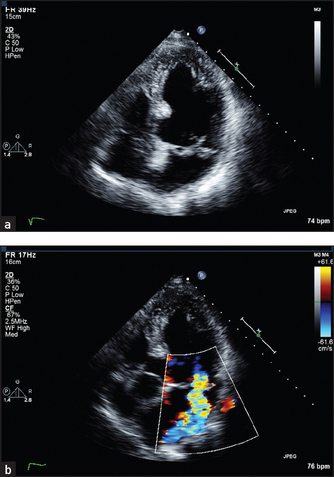

• In two-dimensional or sector scanning, ultrasound information is assembled into a moving picture that shows the relationship between different areas of the heart in a series of two-dimensional slices (see Figures 8.15 and 8.16 below). This gives information about valve appearance, cardiac function and the presence of congenital abnormalities.

Figure 8.15 Normal long-axis view of the heart The mitral valve leaflets can be seen wide open in this diastolic frame. The apex of the heart is on the left and the right ventricle is at the top of the picture. (From Baker T, Nikoli

G, O’Connor S, Practical cardiology, 2nd edn. © 2008, Sydney: Elsevier Australia.)

Figure 8.16 Normal four-chamber view of the heart. The left atrium and ventricle are on the right side of the picture. The AV (mitral and tricuspid) valves are closed in this systolic frame. (From Baker T, Nikoli

• In continuous and pulsed wave Doppler, interrogation of the returning ultrasound signal enables calculation of the Doppler shift caused by reflection of the beam from moving columns of blood. This means that the velocity and direction of blood flow from different parts of the heart can be measured. The Doppler signal can be displayed as a velocity wave. By superimposing the Doppler callipers on the two-dimensional image, the echocardiographer is able to measure the velocity of jets of blood from a particular area (e.g. in the ascending aorta just beyond the aortic valve cusps; see Figure 8.17).

Figure 8.17 (a) Four-chamber view of a patient with prolapse of both mitral valve leaflets. This systolic frame shows the closed mitral leaflets (anterior on the left) bowing back into the left atrium as they face the full force of left ventricular systole. (b) Four-chamber view of a 50-year-old woman with a middle and late systolic murmur. A brightly coloured (high-velocity) jet is seen in this systolic frame, extending from the centre of the mitral valve well back into the left atrium. (From Baker T, Nikoli

The echo also allows the left ventricle to be examined for areas of segmental hypokinesis (reduced wall motion) the presence of which suggests previous infarction as the cause of the cardiac failure. Figure 8.16 shows the structures seen in the four-chamber view of the heart. Here the echo transducer scans the heart from the position of the apex beat.

Sector scanning and M mode pictures can provide information about valve morphology, for example thickening or prolapse of the leaflets (see Figure 8.17). Doppler echo can reveal abnormal jets of blood, for example regurgitant jets, and measure flow velocity across valves. This measurement can be used to estimate the valve gradient (the difference in pressure across the valve).

3. Mitral regurgitation and mitral valve prolapse. Here the mitral valve may appear abnormal and abnormal coaptation of the leaflets may be visible (see Figure 8.17).